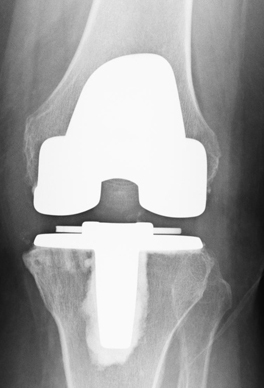

(常規(guī)全膝關(guān)節(jié)置換術(shù)后X光片)

微創(chuàng)膝單髁置換術(shù)與全膝關(guān)節(jié)置換術(shù)相比,優(yōu)勢(shì)十分明顯。微創(chuàng)膝單髁置換術(shù)具有手術(shù)切口小,損傷小,出血少,無(wú)需輸血;術(shù)后疼痛少,術(shù)后第2天即能下地行走,術(shù)后3天可以出院。2017年6月以來(lái),柳州市人民醫(yī)院關(guān)節(jié)骨病運(yùn)動(dòng)醫(yī)學(xué)科以彭偉秋博士為首的團(tuán)隊(duì),積極學(xué)習(xí)和引進(jìn)新技術(shù),在柳州市率先成功開(kāi)展了膝關(guān)節(jié)單髁置換手術(shù)。柳州380萬(wàn)人口中20%是60歲以上老人,76萬(wàn)老人中約有50萬(wàn)老人患有老年性膝骨性關(guān)節(jié)炎,其中3%是處于晚期。由于晚期老年性膝骨性關(guān)節(jié)炎致殘,病人無(wú)法生活自理,給家庭和社會(huì)帶來(lái)了較重的負(fù)擔(dān)。我院開(kāi)展的微創(chuàng)膝單髁置換術(shù)實(shí)現(xiàn)了對(duì)晚期膝骨性關(guān)節(jié)炎的精準(zhǔn)優(yōu)化治療,具有康復(fù)快,療效優(yōu),病人樂(lè)意接受等特點(diǎn),為保障老百姓的健康提供了新方案。